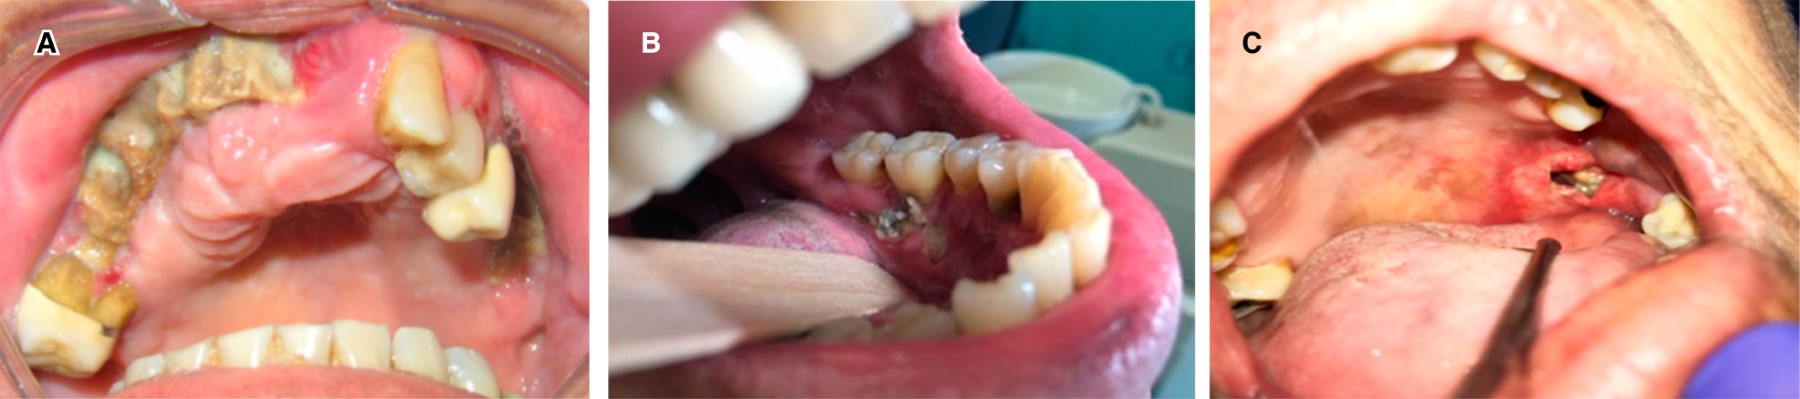

Chemotherapy. Mucositis is the first manifestation in the oral cavity when applying this therapy, consisting in thinning of the oral mucosa, followed by desquamation, erythema and ulceration. Mucositis encourages the entry of microorganisms that cause some systemic infections. This can be considerably reduced by carrying out a proper dental management. When only CT is applied, the oral effects appear from 40 to 70%. Applying both therapies, CT and RT, oral effects are increased by up to 90%, especially if the area to radiate covers the oral cavity.6 Some cases of oral CT effects are shown in Figure 2.

As support in the treatment of CT, bisphosphonates (BP) have recently been used because they inhibit osteoclast production and decrease bone resorption; they are used to control bone metastases and osteolysis (decalcification) in advanced cancer. There are oral and intravenous BPs (zoledronic and pamidronic acids). Intravenous BP can cause the adverse side effect, the osteonecrosis in jaw. A side risk factor in development of osteonecrosis in jaw is a bone trauma as surgical tooth extraction (the most common). Sometimes bone necrosis can occur spontaneously. Dentist in charge should be informed of the osteonecrosis associated with BP and should keep communication with the oncologist who takes care of the case.8,9 Cases of osteonecrosis due to BP are shown in Figures 3 and 4.